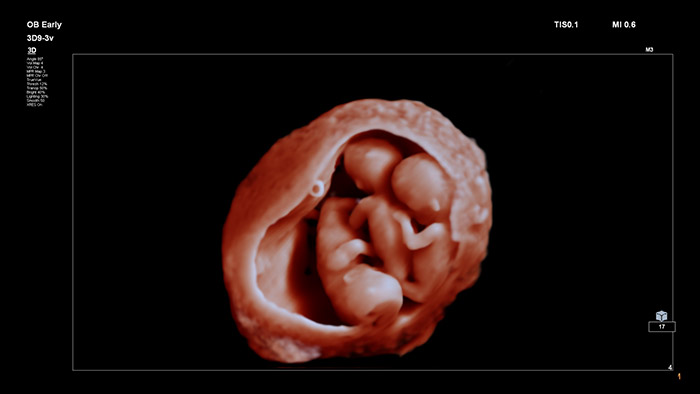

TrueVue è in grado di fornire a medici e gestanti immagini innovative, altamente dettagliate, incredibilmente realistiche del feto durante la gravidanza, grazie anche alla possibilità di manipolare in maniera flessibile una sorgente luminosa virtuale.